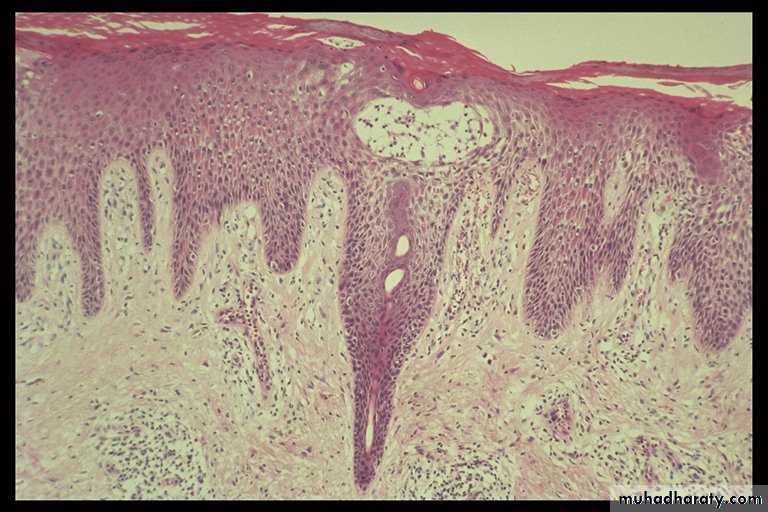

Себорейный гиперкератоз что это гистология - фото презентация